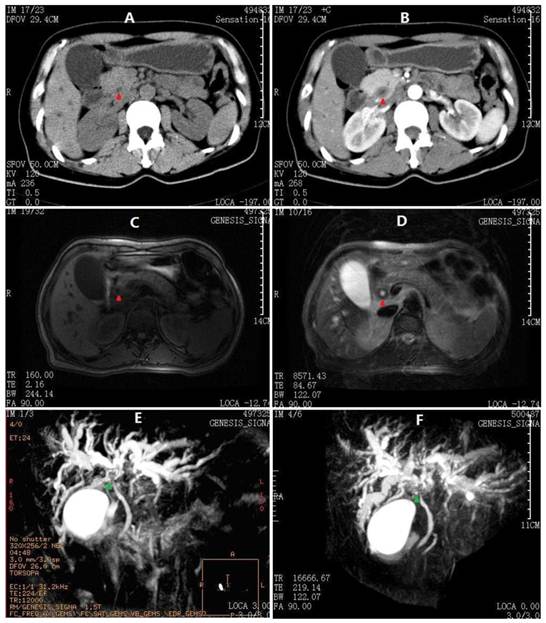

Fig 1

Abdominal CT and MRCP images at 1st admission. A) Thicken cystic neck, cystic duct and CBD (red arrowheads) on plain scan. B) CBD contrast enhancement in a pattern of concentric circles. C) Axial T1-W image showing moderate dilatation of intrahepatic biliary radicals in both lobes of the liver with extrahepatic bile ductal thickening. D) Axial T2-W image showing hypointense gross circumferential mural thickening of the CBD. E) The first MRCP performed before ERCP showing dilated intrahepatic ducts with abrupt cut-off of their lumens in the hilum (green arrowheads). The main pancreatic duct is not observed. F) Second MRCP after ERCP showing more dilated intrahepatic ducts with hilar discontinuity. The proximal main pancreatic duct is also observed, whereas the distal duct is not indicated.

On physical examination, she was a well-developed woman with a body weight of 54 kg (body mass index: 20.6 kg/m2), although she had lost 10 kg over the last 4 months. Her vital signs were stable and within normal limits, and no positive physical exam findings except scleral icterus were present. Her complete blood count, coagulation factors, erythrocyte sedimentation rate, serum immunoglobulin, CEA, AFP and CA125 were normal, whereas anti-hepatitis viruses (A-E), anti-HIV and abnormal autoimmune antibodies were negative. Urine and stool tests were consistent with obstructive jaundice. The liver function tests and CA19-9 results are summarized in Table 1. Moreover, the flow cytometry lymphocyte subpopulations were normal at 49% CD3+, 21% CD4+, 23.4% CD8+, and 19.5% natural killer cells (TBNKTM, Latonia, KY). Her chest CT, gastroscopy and colonoscopy demonstrated no abnormalities, although abdominal ultrasonography revealed extra- and intrahepatic biliary dilatation. The outer CBD diameter was dilated to 16.1 mm as its maximum, but the lumen was narrowed to almost zero due to an irregular thickened wall (7.4 mm at its maximum). No findings that were consistent with bile duct calculus, liver neoplasm or cirrhosis were identified. Furthermore, an abdominal contrast-enhanced CT scan and an MRCP produced similar findings, i.e., a hilar biliary stricture with no evidence of abdominal masses or lymphadenopathy (Fig. 1). Accordingly, an ERCP was performed, which revealed an isolated irregular proximal CBD stricture with dilated intrahepatic biliary trees and no duodenal or ampullary tumors as well as negative brush cytology (Fig. 2A). After a multidisciplinary consultation with the gastroenterologists, radiologists and oncologists, a consensus diagnosis of primary sclerosing cholangitis rather than cholangiocarcinoma was made, partly due to the lack of malignant features consistent with cholangiocarcinoma in all of the medical images. Thus, the patient was transferred to the Gastroenterology Dept. and received a conventional diagnostic plan of glucocorticoid-free treatment. Unfortunately, within the first week posterior to the ERCP, her hyperbilirubinemia worsened, with TBil and DBil increasing to 203.5 μmol/L and 123.1 μmol/L, respectively. At that time, a repeat MRCP revealed a more indistinct biliary bifurcation and CHD, which was pathognomonic for malignancy (Fig. 1F). Therefore, a hepatic hilar cholangiocarcinoma (Klatskin tumor) emerged as the new presumptive diagnosis, and thus, an exploratory laparotomy was scheduled after comprehensive consent was obtained.

From the perspective of preoperative diagnosis, it is relatively difficult to reach a precise decision. The clinical manifestations are almost not specific, presenting an unknown cause of biliary wall thickening and obstructive jaundice. Radiologically in this case, the thickened CBD exhibits a contrast enhancement in a pattern of concentric circles on the CT scans, and shows a hypointense gross circumferential mural on the axial T2-W MRI images; these may be the characteristic features of biliary cryptococcosis, according to past experiences from the systemic cryptococcosis with hepatobiliary involvement [8-13]. However, an important difference between this case and the disseminated cryptococcosis is the absence of lymphadenectasis, which just verifies the circumscription within the biliary system. The main differential diagnoses are listed in Table 2. In terms of treatments, a surgical intervention was necessary for this patient, as it was impractical to obtain reliable pathological data on bile ducts except during surgery. Analogously, biliary obstructive lesions should be treated as cholangiocarcinomas, whenever a malignancy is not definitely excluded [17].